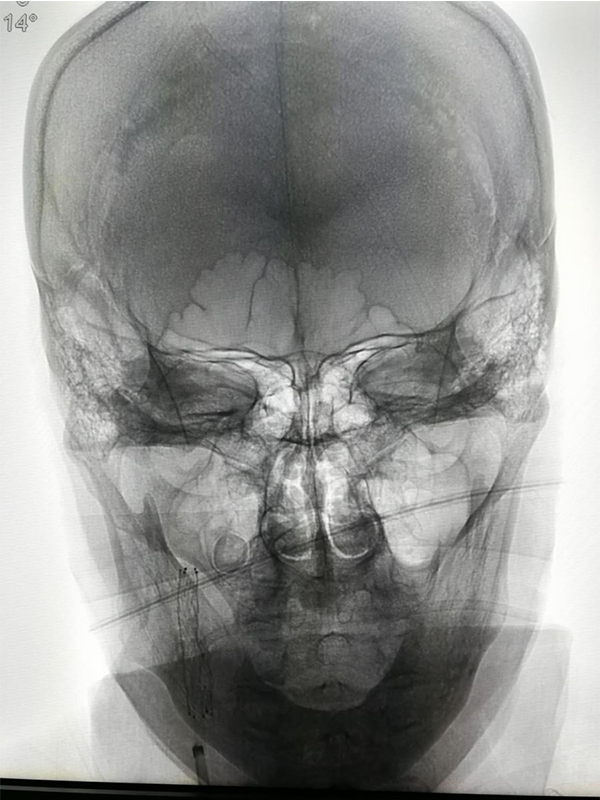

CT MRI MRA( Toast 1

MRA CTA (CT ) DSA <50 %) MRA 50 % CTA 80% DSA 99 % ( ) CTA DSA

MRA CT CTA